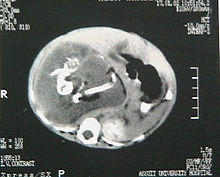

Computed Tomography scan of the patient's abdomen reveals a large retroperitoneal soft-tissue mass. There are long hyperdense opacities that resemble fetal bones.